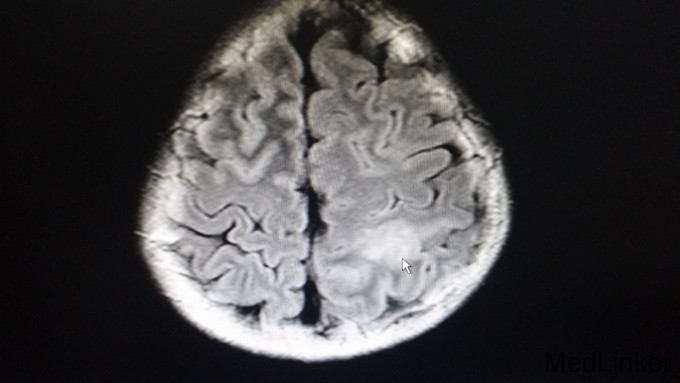

查体:脑膜刺激征阳性:Kernig征阳性,颈抵抗,颏胸距4指。辅助检查: 1. 血常规:白细胞19.02G/L,中性粒91.4%,血沉26mm/h;凝血6项纤维蛋白原4.08g/L,D-二聚体1.31mg/L;生化八项、脑脊液常规、生化、细菌、真菌未见明显异常,脑压240mmH20; 2. 脑电图:痫样放电,中度异常脑电图; 3. CT:双侧额叶纵裂旁灰质、双侧岛叶、右额叶上部及左顶叶多处灰质异常信号。 4. 外院T-spot试验阳性。